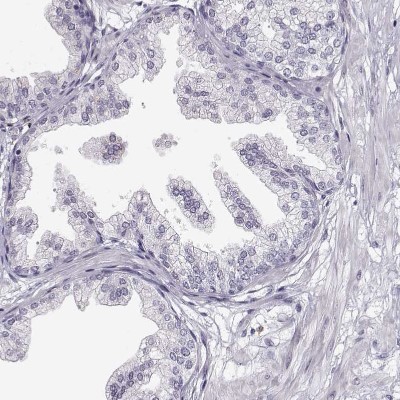

- Immunohistochemistry-Paraffin: VGF Antibody [NBP2-31596] - Staining of human placenta shows no positivity in trophoblastic cells as expected.

- Submitted by